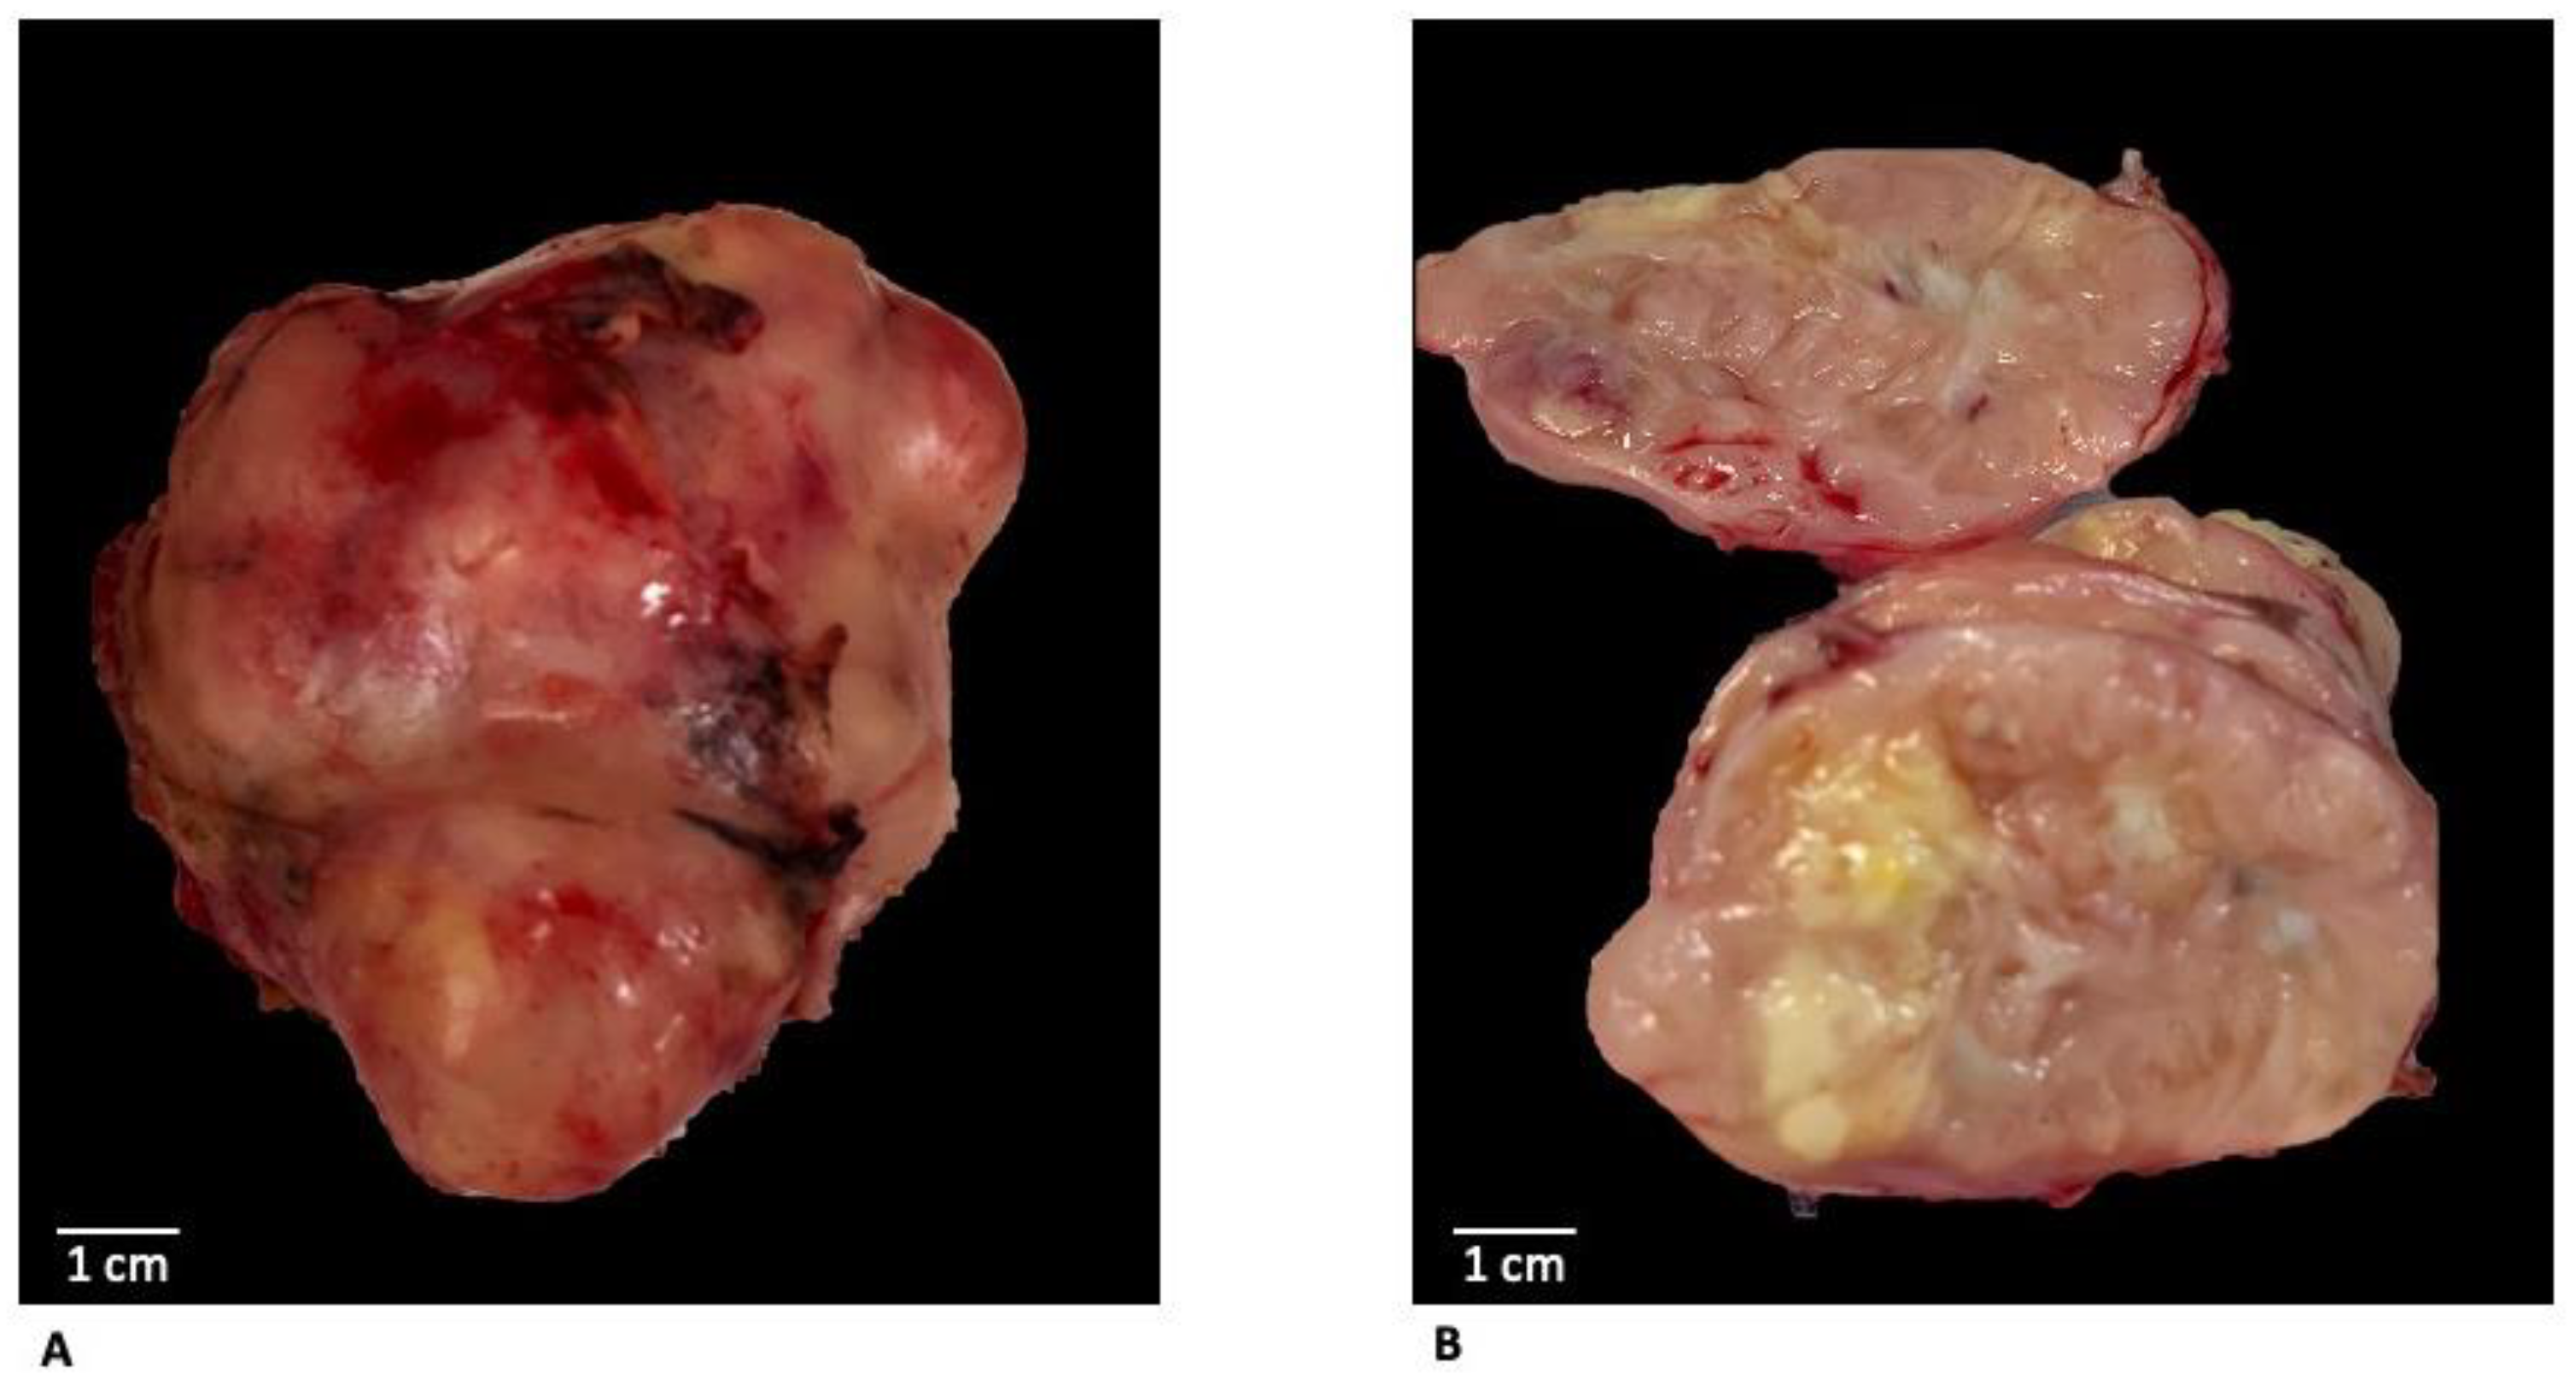

A large polylobate irregularly shaped mass tan to brown was revealed on macroscopic examination; the cut surface showed a whorled pattern admixed with yellowish areas of necrosis and areas of hemorrhage (Figure 3).

Figure 3. Macroscopic examination after surgical excision showed a large polylobate irregularly shaped mass (A) tan to brown with a sharp margin and smooth profile; the cut surface (B) showed a whorled pattern admixed with yellowish areas of necrosis and areas of hemorrhage.